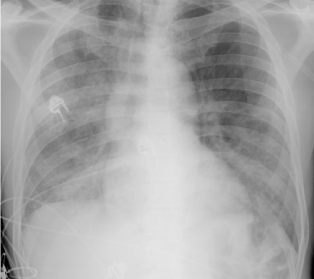

A 25-year-old man comes to the emergency department due to 3 weeks of progressive dyspnea on exertion, dry cough, fatigue, intermittent fever, and chills.  He was treated for genital herpes several years ago but otherwise has no significant medical history.  The patient does not use tobacco or illicit drugs but occasionally drinks alcohol.  He has been in a monogamous relationship for the past year and had multiple partners previously.  Temperature is 38.7 C (101.7 F) , blood pressure is 130/80 mm Hg, pulse is 90/min, and respirations are 28/min.  Pulse oximetry is 88% on room air.  Scattered white plaques are present on the oropharyngeal mucosa.  Lung auscultation reveals bilateral, diffuse crackles.  Chest x-ray is shown in the image below. A 25-year-old man comes to the emergency department due to 3 weeks of progressive dyspnea on exertion, dry cough, fatigue, intermittent fever, and chills.  He was treated for genital herpes several years ago but otherwise has no significant medical history.  The patient does not use tobacco or illicit drugs but occasionally drinks alcohol.  He has been in a monogamous relationship for the past year and had multiple partners previously.  Temperature is 38.7 C (101.7 F) , blood pressure is 130/80 mm Hg, pulse is 90/min, and respirations are 28/min.  Pulse oximetry is 88% on room air.  Scattered white plaques are present on the oropharyngeal mucosa.  Lung auscultation reveals bilateral, diffuse crackles.  Chest x-ray is shown in the image below.   Arterial blood gas shows a PaO<sub>2</sub> of 60 mm Hg and a PaCO<sub>2</sub> of 33 mm Hg.  Induced sputum microscopy shows few leukocytes and no predominant organism.  Which of the following is most likely to be effective for this patient's pulmonary condition? A) Ceftriaxone and azithromycin B) Isoniazid, rifampin, pyrazinamide, and ethambutol C) Liposomal amphotericin B D) Trimethoprim-sulfamethoxazole and prednisone E) Vancomycin and piperacillin-tazobactam Arterial blood gas shows a PaO2 of 60 mm Hg and a PaCO2 of 33 mm Hg.  Induced sputum microscopy shows few leukocytes and no predominant organism.  Which of the following is most likely to be effective for this patient's pulmonary condition?